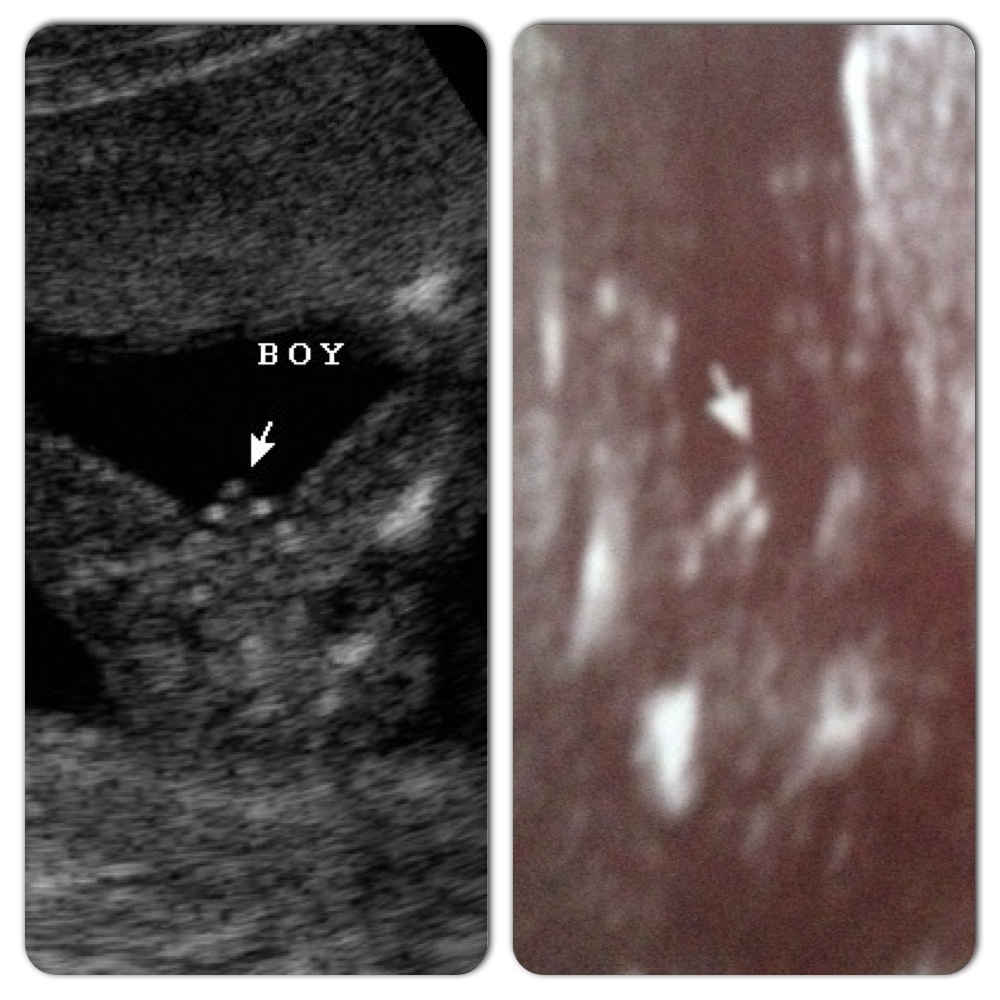

both of these comparison shots are what have me wondering still: Attachment 15437Attachment 15438

both of the pictures (including the left hand one labeled "boy") are confirmed girls.

I wouldn't say hopeless, but sticking out a little far for a girl...